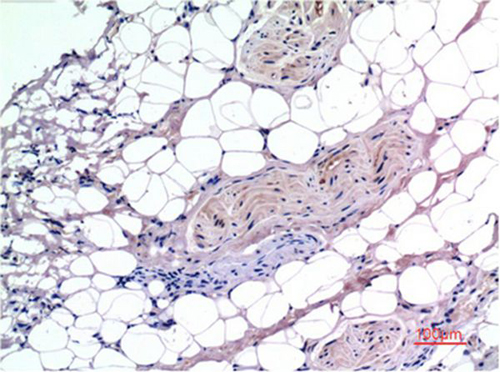

IHC (Immunohistochemisry)

(Immunohistochemical analysis of paraffin-embedded Human Breast Carcinoma Tissue using Smad3 Mouse mAb diluted at 1:200.)